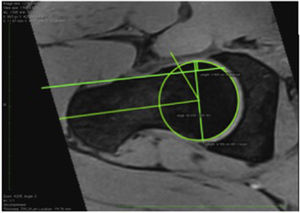

La lesión tipo cam fue evaluada por una medida del ángulo alfa en la reconstrucción axial oblicua, entre el eje del cuello femoral y una línea que conecta el centro de la cabeza femoral con el punto de inicio de esfericidad del contorno cabeza-cuello. Sujetos con ángulo alfa > 55° fueron diagnosticados con lesión tipo cam17-20.

El diagnóstico de lesión tipo pincer fue determinado principalmente por la medición del ángulo centro borde > 39° (CEA), que es un indicador de excesiva cobertura acetabular. El CEA fue medido en el plano coronal entre una línea vertical pasando a través del centro de la cabeza femoral y otra línea desde el centro de la cabeza femoral al acetábulo lateral21-23.